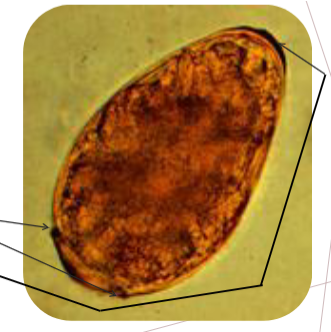

schistosoma haematobium egg

112-180 x 40-70 um

Oval

Prominent terminal spine

Note developing embryo

Usually found in urine